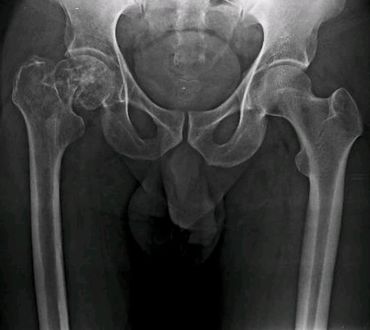

Reemplazo total de cadera no convencional por inflitración tumoral del tercio proximal del femur